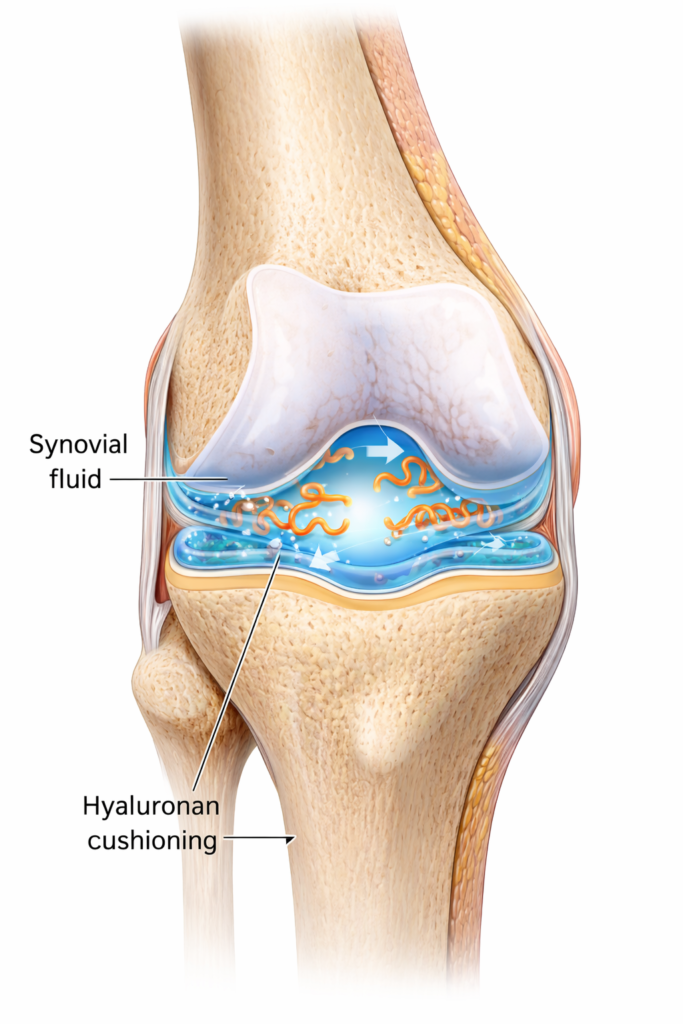

The loss of joint cushioning due to declining Hyaluronan levels.

This natural “joint lubricant” is responsible for keeping your movements smooth, flexible, and pain-free.

Hyaluronan is a gel-like, cushion-building molecule that:

- Lubricates joints

- Keeps cartilage hydrated

- Reduces friction

- Supports smooth movement

- Promotes flexibility

Think of hyaluronan like “oil for your joints.”

Without it, the joint becomes a dry hinge that grinds and hurts.

But with enough HA, your joints move like they did in your youth.

Your natural HA production drops by 50% after age 40.

Reduces synovial fluid flow.

Joint Genesis contains a patented ingredient called Mobilee®, which increases hyaluronan levels by up to 10X.

- More joint lubrication

- Better cushioning